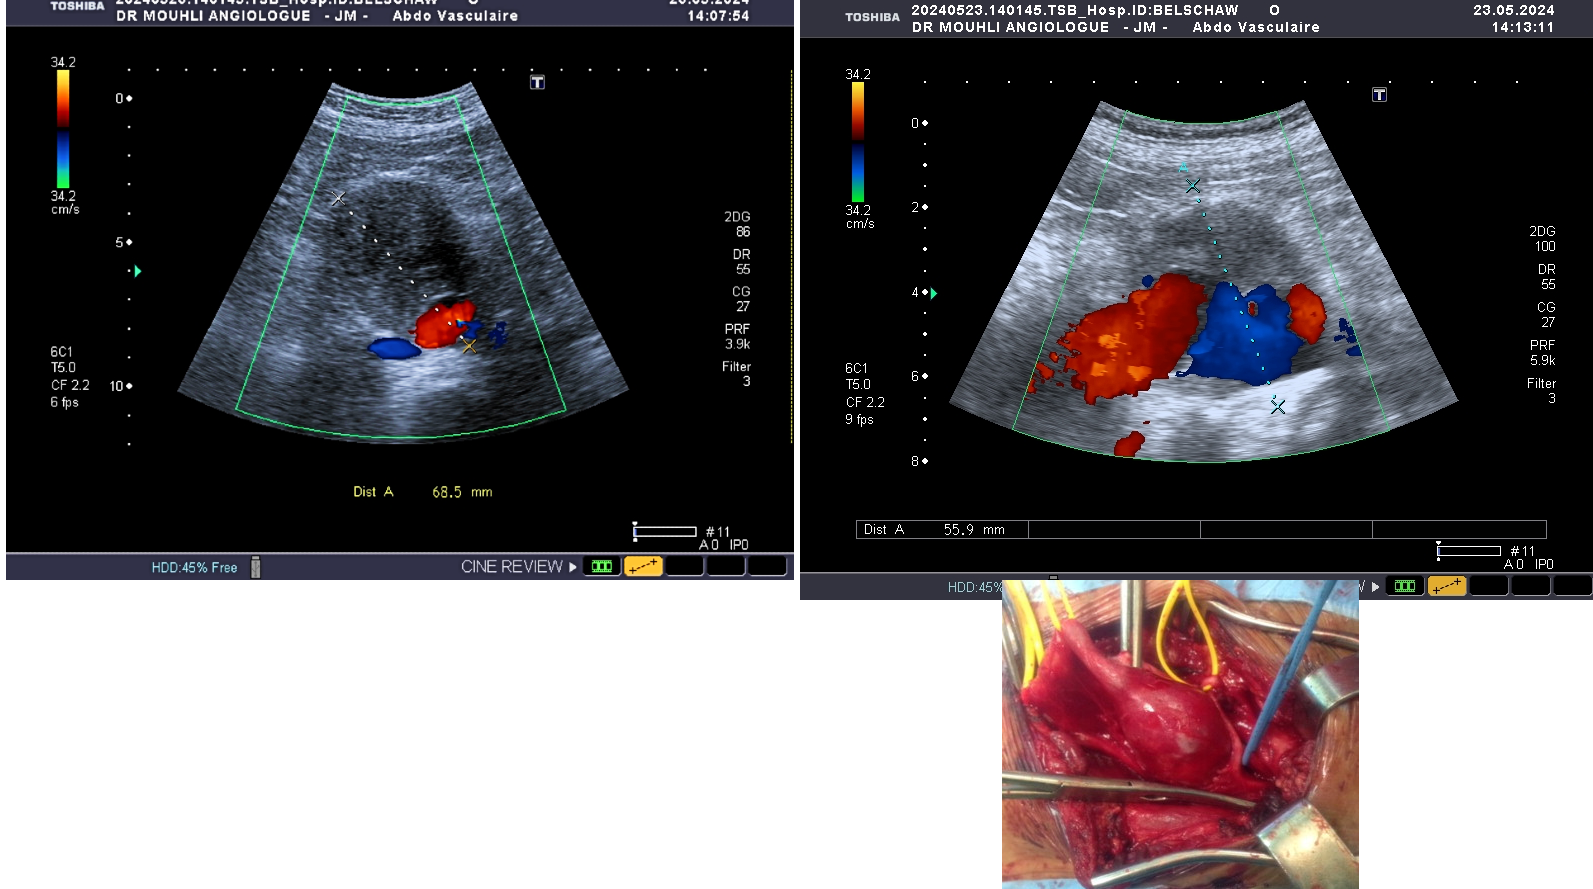

L’anévrisme aortique est une maladie de l’aorte consistant en une dilatation de cette dernière. Elle peut concerner n’importe quel segment de ce vaisseau. La forme la plus fréquente est l’anévrisme de l’aorte abdominale en dessous des artères rénales